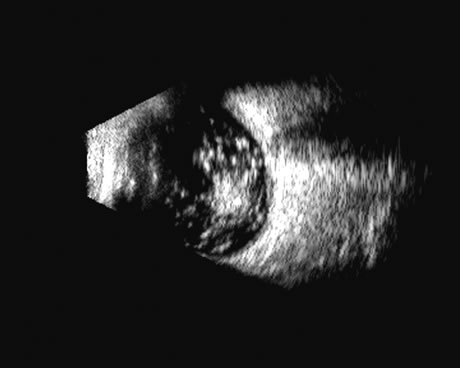

Fig. 4. A clinically well-placed posterior chamber intraocular lens nevertheless had patient complaints of photophobia and irritation due to a folded haptic (arrow).

Fig. 5. An anterior chamber intraocular lens has had the support haptics dislocate posterior to the iris plane and can be seen as typical foreign body echogenic reflections (arrows).